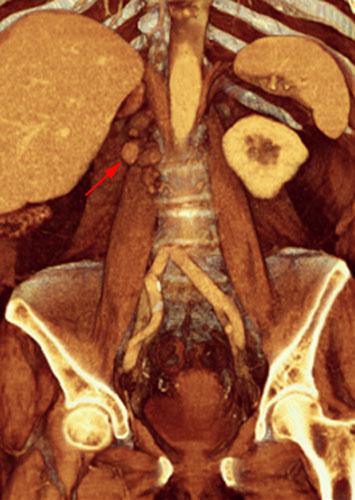

Recidiva adenopática de hipernefroma